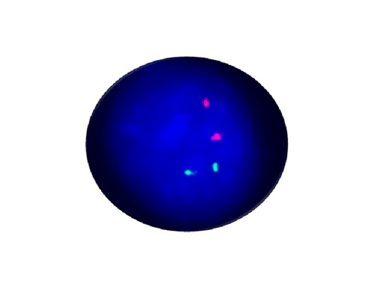

ASPSCR1/TFE3 Fusion Positive

Probe Description: ASPSCR1/TFE3